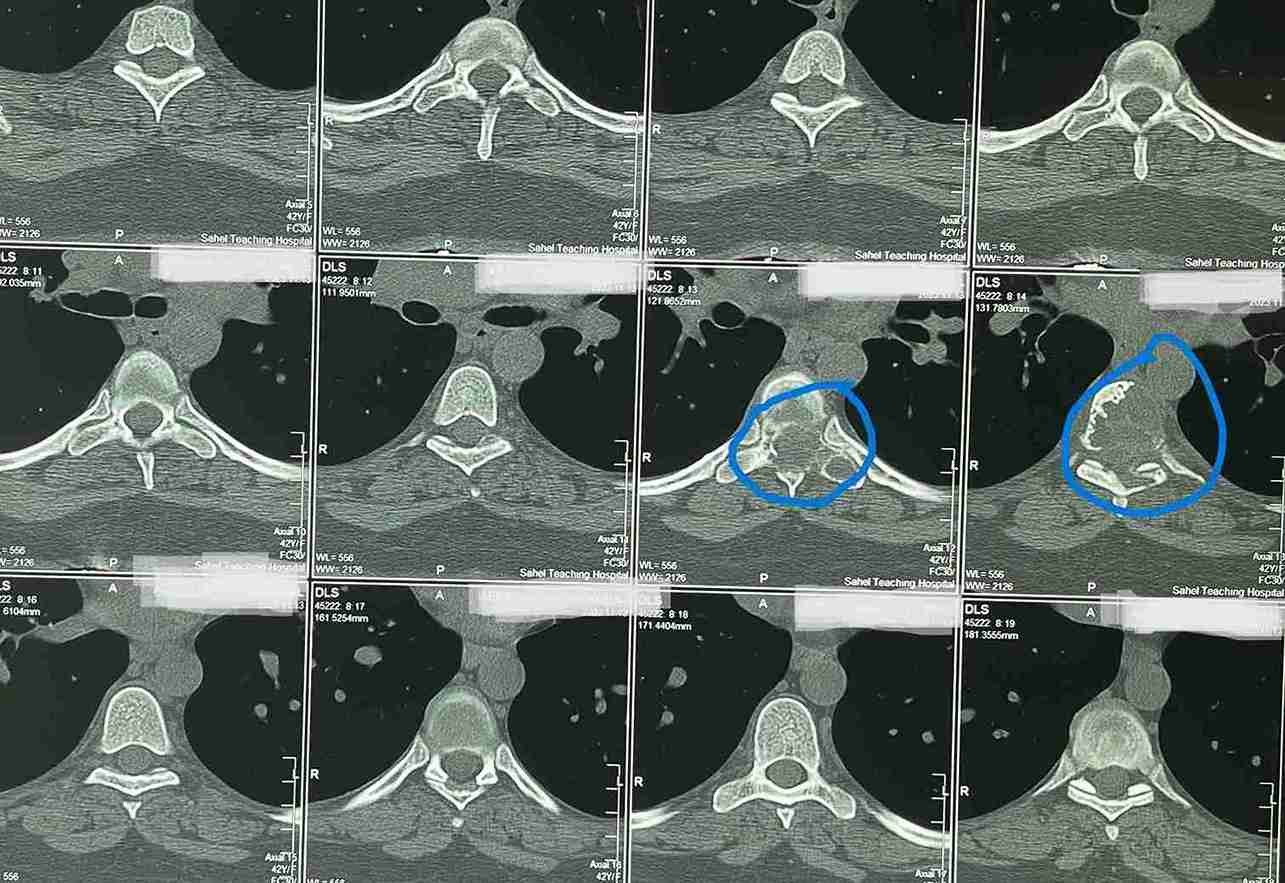

43-year-old female patient suffers from increasing weakness in the lower extremities

A 43-year-old woman suffering from progressive weakness in both lower limbs was diagnosed and treated. This condition affects walking ability and mobility, requiring thorough neurological evaluation to determine the underlying cause and develop an appropriate treatment plan.